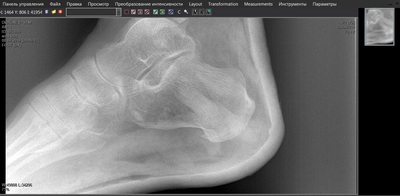

Ударно-волновая терапия. Очень болезненно, но помогло. И да, при шпорах рентген пятки необходим. Заверните 2, пожалуйста.